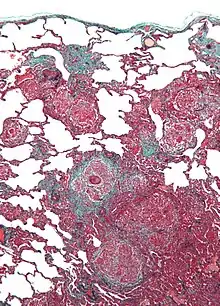

Micrograph of hypersensitivity pneumonitis, the histologic correlate of bird fancier's lung. Lung biopsy. Trichrome stain. | |

Lung biopsy usually reveals non-necrotizing granulomatous inflammation.[7] It also shows "foamy" macrophages and crystals of oxalic acid.[3] Hyperplasia tends to occur in type 1 pneumocytes and not in type 2 pneumocytes.[3]